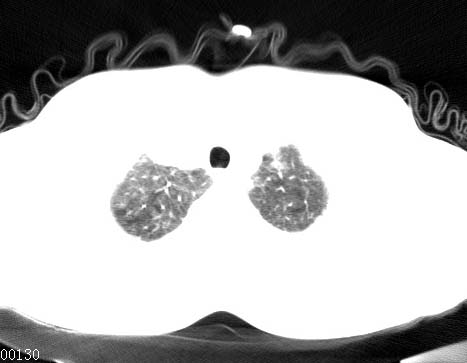

男性 病人 30岁,活动后气促2月余.隔疝伴胸腔积液.右上肺结核!

双肺上结核;膈肌裂孔疝。

左侧胸腔积液,并胸腔内见多个含液 气组织,并相互重叠。影像特征很特殊,应该是“膈疝”。支持!

左侧膈疝,及左侧胸水,双上肺结核。

支持!左侧膈疝,左侧胸水,双上肺结核。